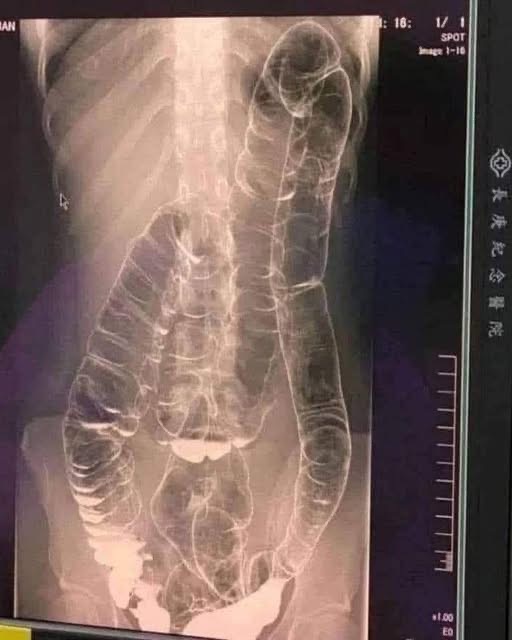

In this case, medical imaging revealed a severely distended colon that had enlarged so much it reached up toward the chest, dangerously close to the heart. The stretching had nearly erased the colon’s natural folds and wrinkles, essential for its proper function.

Left untreated, this condition could have led to life-threatening complications.